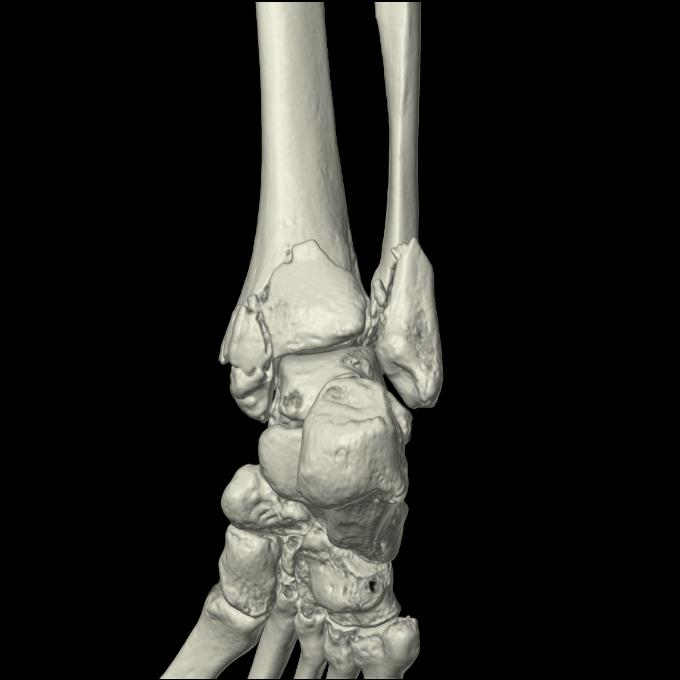

102755 1/4 2R 1/15 2R 右足関節 68歳女性 右三果脱臼骨折